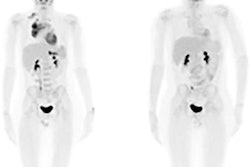

PiB-PET images display Down syndrome-specific templates for carrying capacity (K) and nonspecific Down syndrome (NS) binding. Maps of gray and white matter are displayed for visual reference. K images represent the theoretical limit for the Down syndrome brain to carry beta-amyloid plaques and are in strong agreement with known spatial distribution of plaques in Down syndrome. The highest values are located in the striatum and precuneus. Images courtesy of Zammit et al and SNMMI.Both SUVr and beta-amyloid load increased with age, and both showed similar changes among study participants who already were PiB-positive or who converted to become PiB-positive, Zammit said. However, among PiB-negative cases, beta-amyloid load provided reduced longitudinal variability compared with SUV ratios.